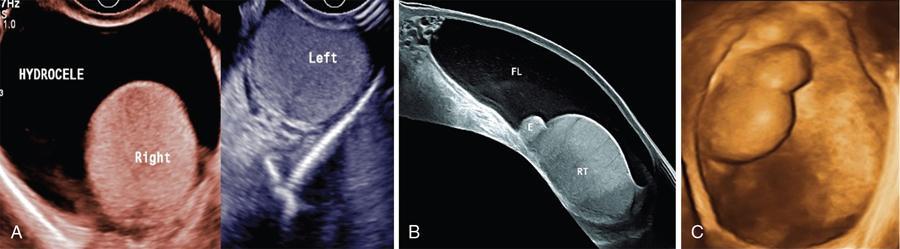

USG findings include empty scrotal sac with UDT usually small, iso- or hypoechoic relative to normal testis. Palpable UDT is most frequently seen in inguinal canal or suprascrotal region just caudal to external inguinal ring (Figs. 11.8.4–11.8.6). Retractile testis at suprascrotal location can be brought down by probe manoeuvre.

Fig. 11.8.3Inguinal US scan of a 2-month-old male child shows undescended right testis (UDT in cursors) at superficial inguinal ring with associated inguinal hernia (RIH). Clinically the child presented with empty right hemiscrotum since birth.

Fig. 11.8.4(A) Scrotal US scan of a 7-year-old male child shows absent right testicle in ipsilateral hemiscrotum, and (B) US scan of right inguinal region shows presence of testicle in inguinal canal (canalicular UDT).

Fig. 11.8.5(A) Scrotal US scan of a 25-year-old male shows absent of both right and left testicles in respective hemiscrotal sacs (empty scrotal sac, s/o bilateral UDT). (B) Suprapubic US scans of the same case of empty scrotal sac showing both right and left testicles lodged in abdominal cavity traced on either side of urinary bladder (bilateral intraabdominal UDT).

Fig. 11.8.6(A) Suprapubic US scan of a 22-year-old male with empty scrotal sac shows bilateral small-sized intraabdominal UDT with microlithiasis. (B) Another case showing intraabdominal undescended left testis (LT) adjacent and medial to iliac vessels and abutting urinary bladder wall.

Visibility of nonpalpable intraabdominally located testis is impaired by bowel gases at US, however, with experienced hands the same can be depicted on ultrasound deep to internal inguinal ring, adjacent to iliac vessels and lateral bladder wall. Tracking the cord technique is also a valuable sign in localizing nonpalpable testis (also ectopic testis) (Fig. 11.8.3).